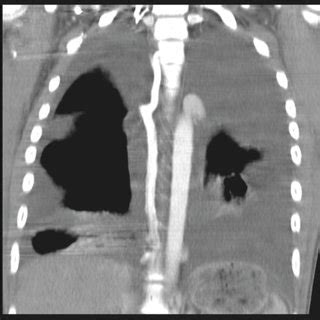

Coronal Plane Ct : Enhanced CT in venous phase in coronal plane. Enhanced CT ... - This can be obtained in a few seconds or less thereby minimising respiratory and cardiac motion artefact.

Coronal Plane Ct : Enhanced CT in venous phase in coronal plane. Enhanced CT ... - This can be obtained in a few seconds or less thereby minimising respiratory and cardiac motion artefact.. A crown in head would define the horisontal plane. The coronal oblique plane is acquired along this dotted red line on the axial shoulder image. Coronal plane imbalance with lateral trunk shift is usually associated with rotational deformity. Coronal plane is a medical term. It more or less corresponds to the plane defined by the frontal bone.